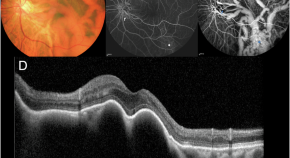

A human eye disease seems to be linked to covert mortality nodavirus, a virus commonly found in aquatic animals. The findings suggest that zoonotic transmission to humans occurs through close contact.